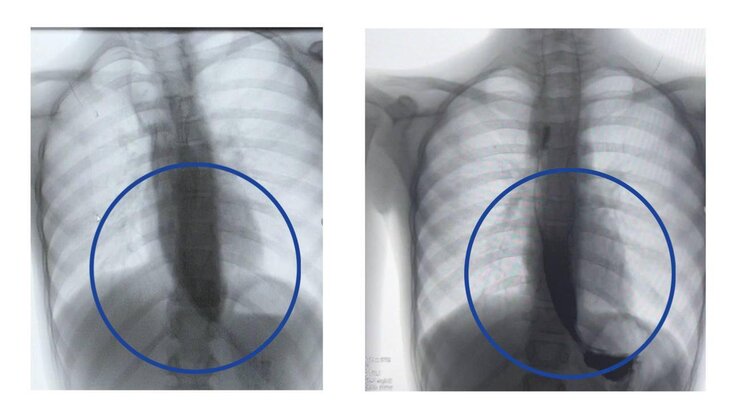

Врачи Детского клинического центра имени Л. М. Рошаля спасли девочку с пятикратным расширением пищевода. Об этом сообщила пресс-служба подмосковного Минздрава.

Девятилетняя девочка поступила в медучреждение с редким заболеванием – ахалазией кардии, из-за которого ее пищевод был расширен почти до 4 сантиметров, когда в норме его диаметр составляет от 7 до 10 миллиметров.

Данная процедура, по его словам, уже доказала свою эффективность у взрослых, однако в детской практике применяется редко. Тем не менее операция прошла успешно, благодаря чему контрастное исследование подтвердило свободное прохождение пищи в желудок уже на следующий день.